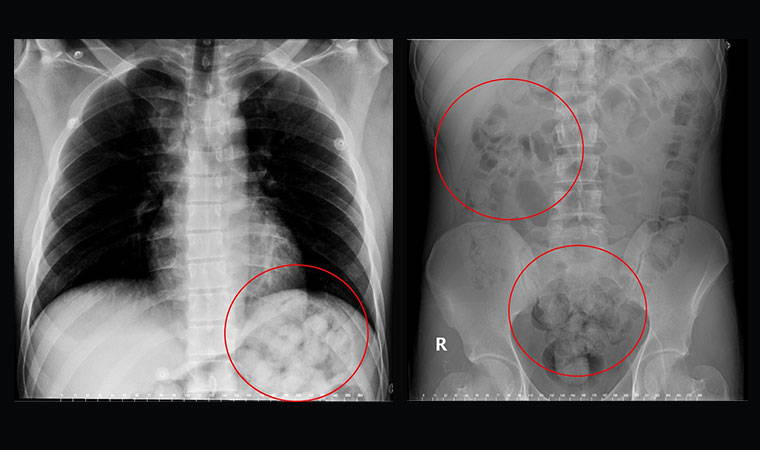

Edinilen bilgiye göre, 5 gün önce Van’dan otobüsle Ankara’ya gelen O. Zahed Ahmed Narziveh rahatsızlanınca hastaneye kaldırıldı. Ankara Şehir Hastanesine getirilen şahsın röntgen görüntüleri gerçeği ortaya çıkardı. Şahsın midesinde 890 gram ağırlığında 2’si patlamış halde 72 kapsül olduğu ve kapsüllerin patlaması ile fenalaştığı belirlendi. Mahkeme kararına istinaden ameliyata alınarak midesindeki metamfetamin kapsülleri çıkartılan zanlı, Ankara Emniyet Müdürlüğüne bağlı Narkotik Suçlarla Mücadele ekiplerince hastanedeki 5 günlük tedavisinin ardından adliyeye sevk edildi.

Van’dan otobüsle Ankara’ya gelen yabancı uyruklu şahıs, yuttuğu 72 kapsül metamfetamin kapsülünün midesinde patlaması üzerine rahatsızlanarak hastaneye kaldırıldı.